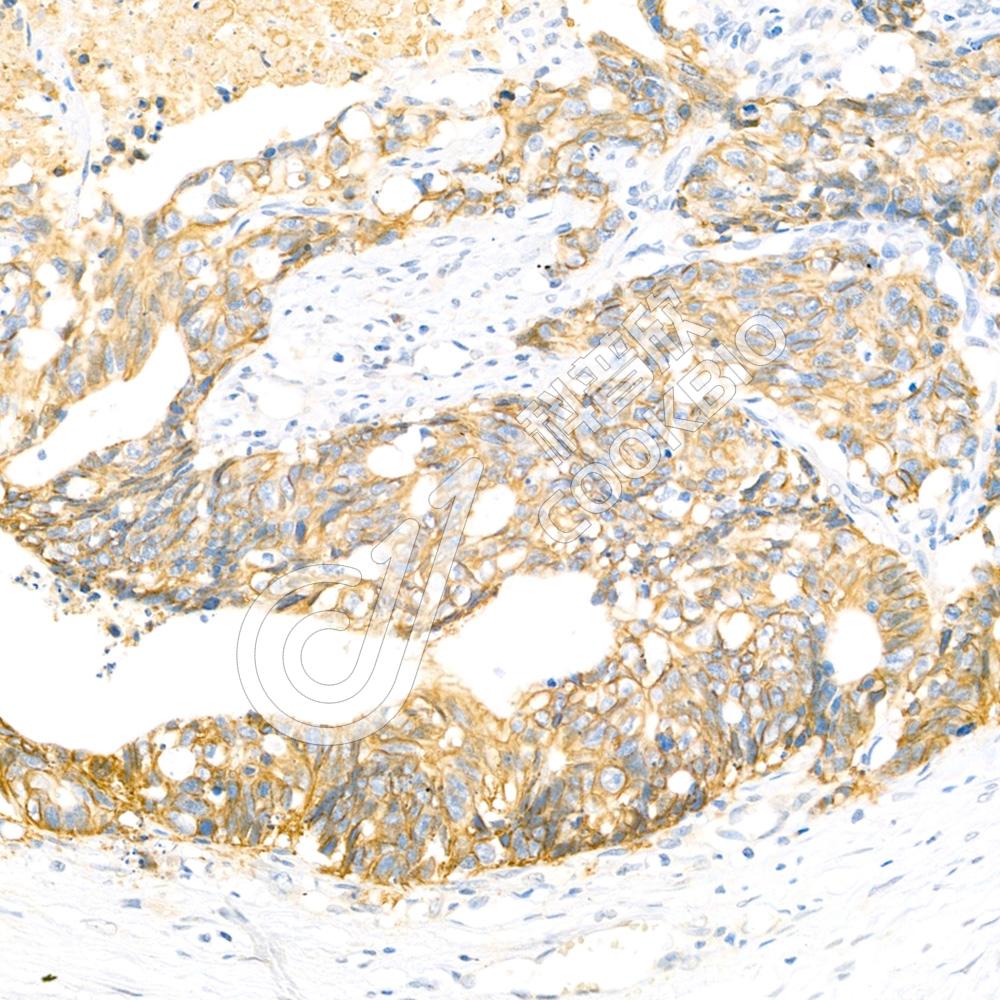

IHC检测PRPH2/RDS蛋白(货号 K1340761).

样品: 大鼠眼球, 4%多聚甲醛 (货号KSG1101) 固定12-24小时.

抗原修复: 柠檬酸抗原修复液(干粉, pH 6.0) (KSG1201), 98℃, 20分钟.

—抗: 1: 3000稀释, 4℃ 孵育过夜.

二抗: S-vision免疫组化多聚二抗(山羊抗兔),即用型 (货号KB3906), 室温孵育20分钟.